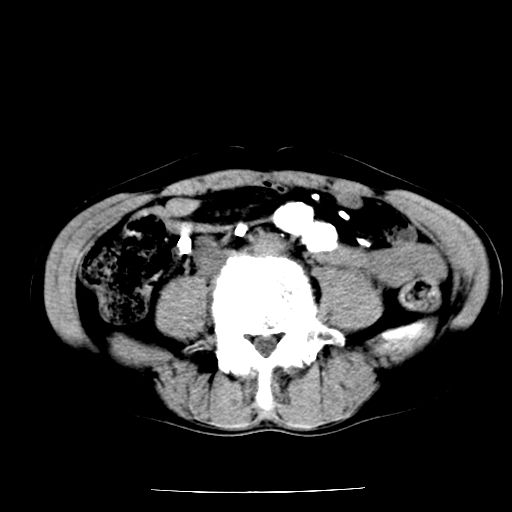

男,59岁,“结核性胸膜炎”30余年,胸部经常疼痛,多次x检查提示“肺部”炎症。腹部疼痛5日,b超提示:“肝内短管结石,余显示不清,建议进一步检查。”

两肺结核并右侧胸腔积液;脾脏、腹腔及腹膜后淋巴结结核[陈旧性];肝内胆管结石

胸部腹部都是结核(双肺。纵隔淋巴结,肝脏,脾脏,肠系膜)

两肺结核并右侧胸腔积液;脾脏、腹腔及腹膜后淋巴结结核[陈旧性];肝内胆管结石。直肠息肉?